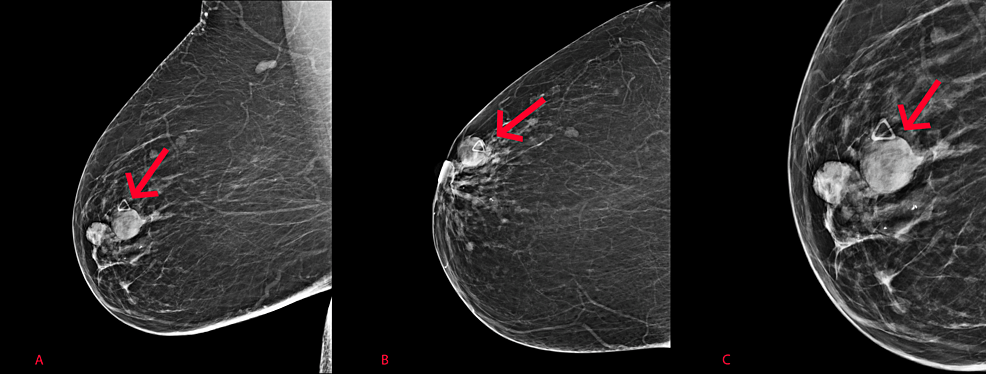

Діагностика папілом молочної залози у Харкові

Перед початком лікування папілом молочної залози мамолог аналізує скарги пацієнтки та збирає анамнез. Діагностика внутрішньопротокових папілом включає:

- УЗД молочних залоз. Призначається для оцінки структури тканин, встановлення наявності, розміру, виду та кількості патологічних утворень у молочній залозі, огляду регіонарних пахвових лімфатичних вузлів.

За потреби уточнення діагнозу мамолог також може направити на МРТ молочних залоз. Для визначення природи пухлини призначається біопсія під контролем УЗД. Залежно від передбачуваного типу утворення виконуються різні види біопсії (трепан-біопсія або тонкоголкова аспіраційна біопсія).